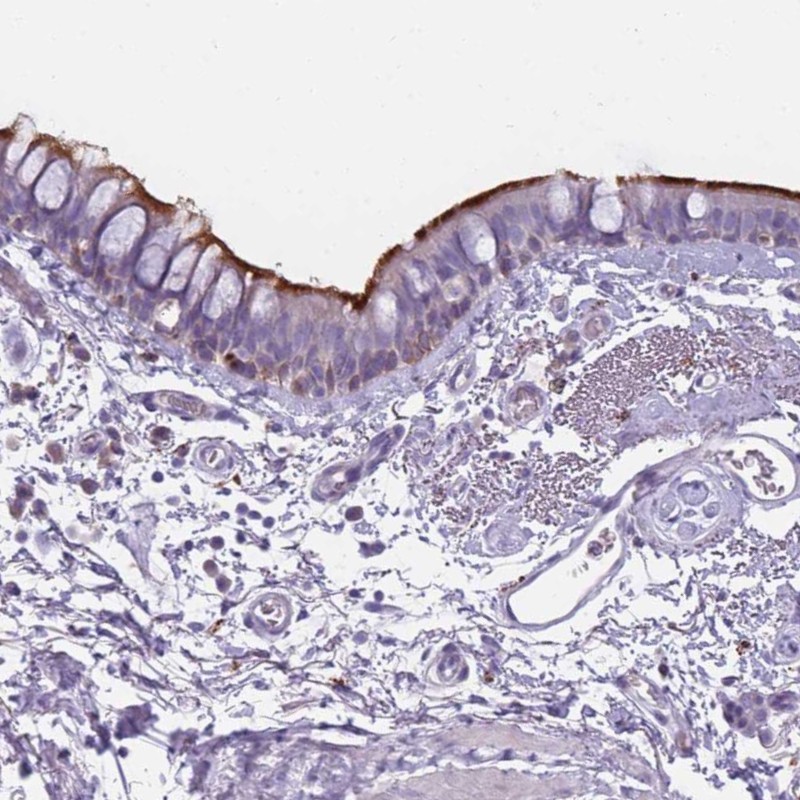

Immunohistochemical staining of human bronchus shows distinct membranous positivity in respiratory epithelial cells.